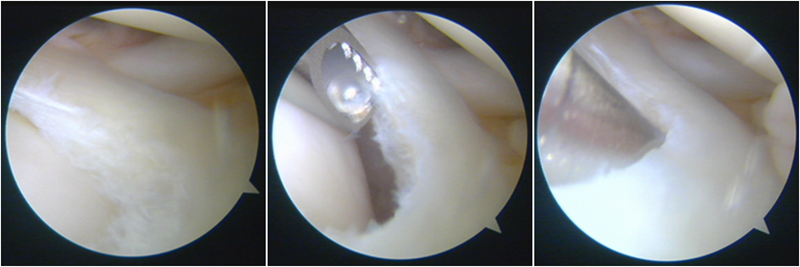

股骨侧保残骨道建立

股骨侧骨道建立,椭圆形扩孔保残9mm

韧带导入过程

送止血带后韧带表明血管膜